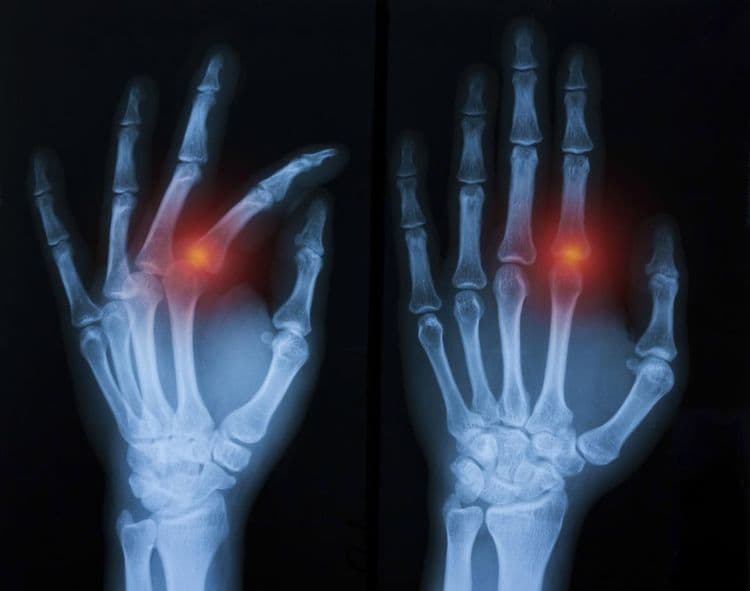

Fracture Dislocation - सांध्यातील एका हाडाला फ्रॅक्चर असल्याने सांधा निखळणे.

IntraArticular Fracture - हाडासोबतच सांध्याचा पृष्ठभाग सुद्धा फ्रॅक्चर होणे.